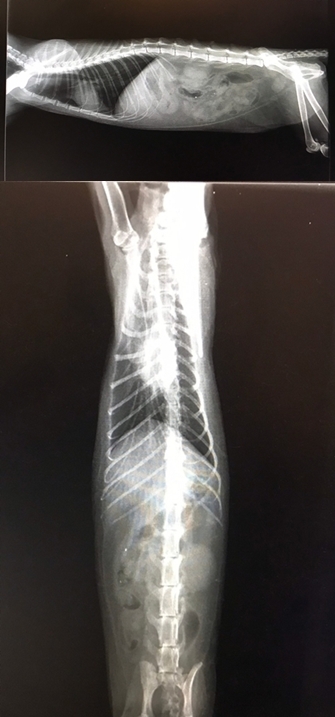

主題: 腦震盪虎斑貓 申請者姓名: 劉素鳳 花色: 申請日期: 2020-06-29 23:28:51 申請者部落格: 申請者臉書網址: https://www.facebook.com/sufeng.liu 所在縣市/合作醫院: 高雄市/弘恩動物醫院 治療費用: 10090元 需求人數: 25人 已結案 (2024-05-31 18:15:17) 報名人員: Kitty Chen x2(已付款)、Claire change(已付款)、Jessy(已付款)、lin789 x10(已付款)、豬妞妞(已付款)、CMBYN(已付款)、tetsuyu x6(已付款)、Evi x3(已付款)、 候補人員: 動物病情說明: 這隻貓咪疑似出了車禍撞到造成腦震盪倒在路邊,發現之後送進合作的醫院治療

醫師給予腦震盪的針劑, 點滴, 灌食等照顧。

希望他能夠快快穩定恢復活力動物近況說明: 貓咪腦壓太高, 造成肺部衰竭, 醫生很努力但還是 回天乏術. 祝福 貓咪沒有病痛了.